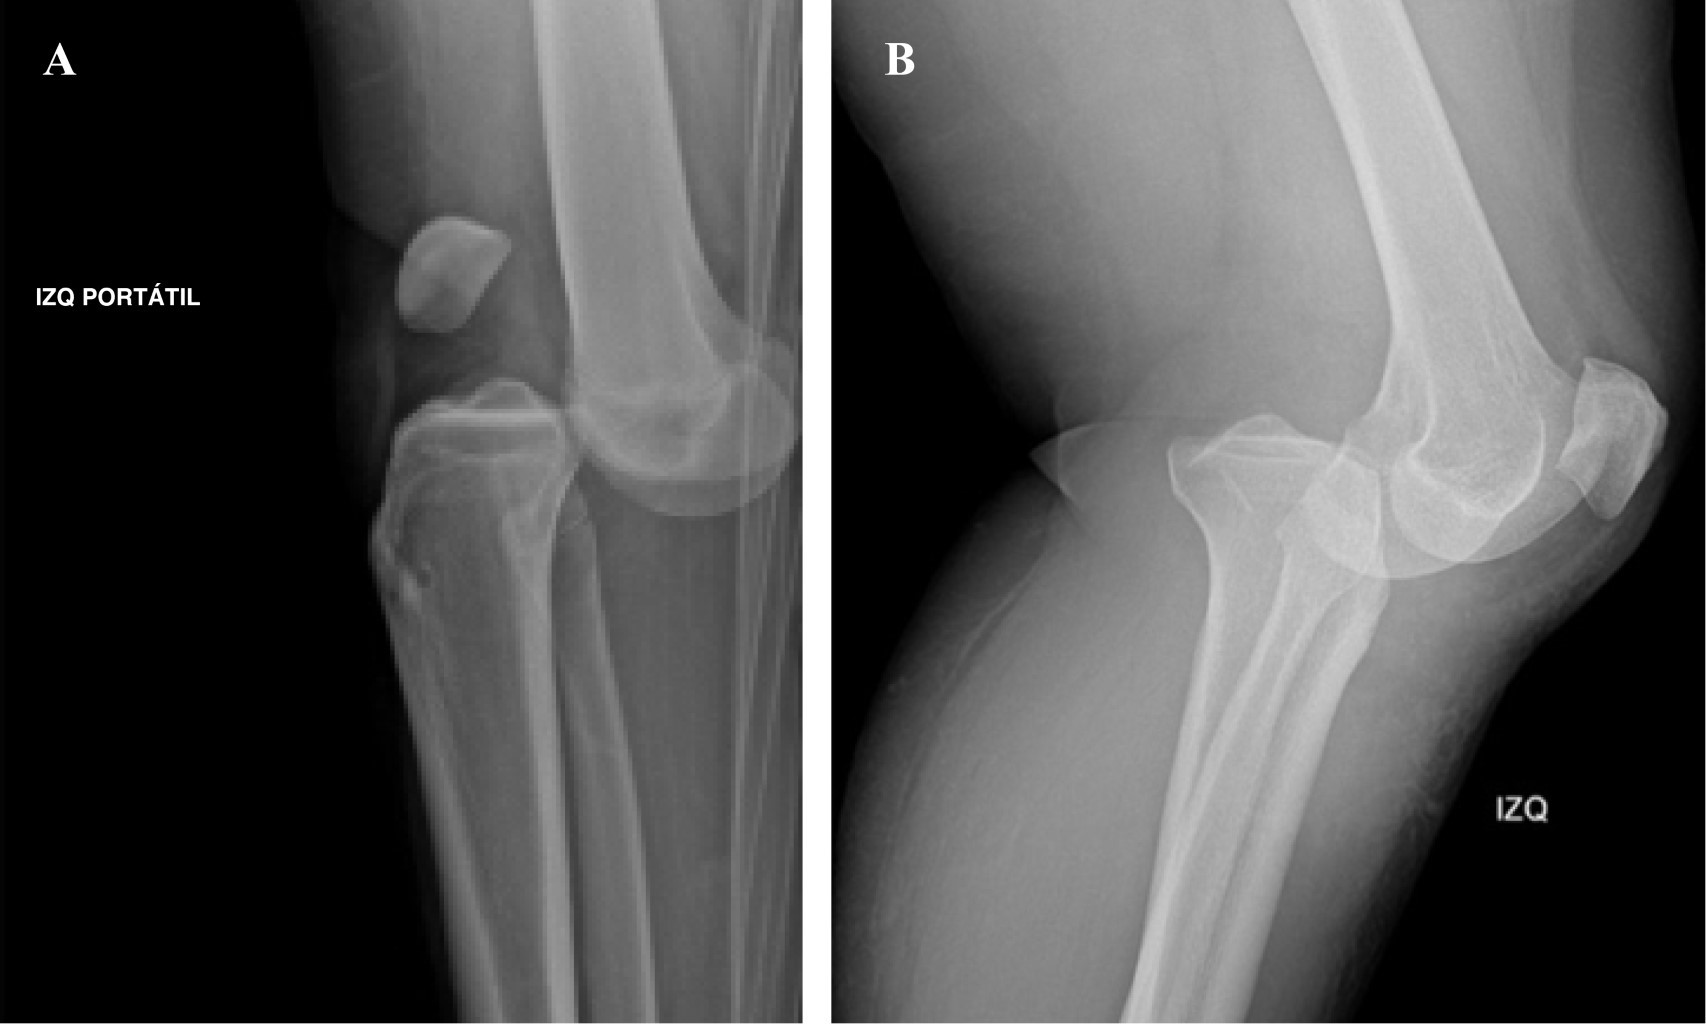

Actualmente las clasificaciones más aplicadas están enfocadas en la identificación y descripción de las estructuras lesionadas y su gravedad para el manejo posterior.21 En 1963 Kennedy fue el primero en clasificar las luxaciones de rodilla según la dirección del desplazamiento tibial en relación con el fémur en anterior (Figura 2A), posterior (Figura 2B), medial, lateral y rotacional.21 Este sistema de clasificación es muy útil para el clínico, en vista de que le permite planear la maniobra de reducción de la rodilla luxada, además de poder alertarlo sobre una posible lesión neurovascular coexistente.21 La principal limitación con este sistema es la variabilidad en los ligamentos lesionados cuando sólo se tiene en cuenta la dirección de la luxación.22

Imagenología: rayos X. El estudio con radiografía simple anteroposterior y lateral en el contexto de la luxación de rodilla se debe dividir en dos escenarios: el primero corresponde al grupo de pacientes que ingresan con una luxación evidente clínicamente, para los cuales las proyecciones AP y lateral son el estudio imagenológico inicial, permitiendo evaluar la dirección de la luxación según la clasificación de Kennedy y así definir el riesgo estimado de lesión vascular, según sea cada caso. Posterior a la realización de las maniobras de reducción es necesario efectuar nuevas proyecciones AP y lateral que permitan evaluar adecuadamente las relaciones de la articulación tibiofemoral en búsqueda de subluxaciones residuales y la presencia de lesiones asociadas (Figura 3).38,39

El segundo escenario es mucho más complejo de abordar, se presenta cuando el paciente ingresa al servicio de urgencias con la rodilla reducida, haciendo del diagnóstico de la luxación de rodilla un reto para el clínico, en el cual las radiografías iniciales tienen un papel valioso en la evidencia de hallazgos característicos que pueden sugerir el diagnóstico de luxación como la apertura de los espacios articulares tibiofemorales (Figura 4), fracturas del cóndilo femoral, fracturas de espinas tibiales anterior y posterior, signo del ligamento arcuato (Figura 5) o el signo de Segond (Figura 6).3